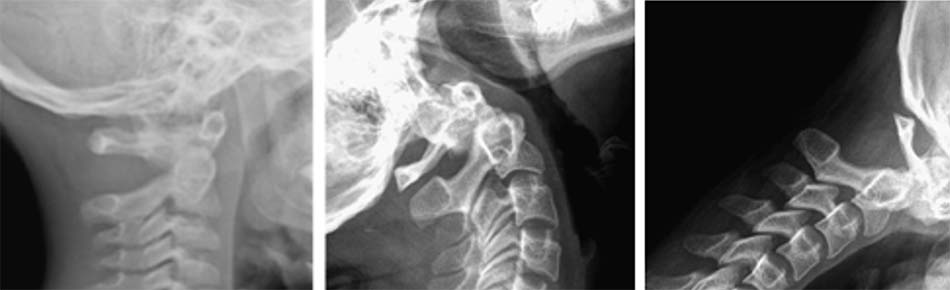

Dựa trên hình ảnh Xquang, cắt lớp vi tính và cơ chế tổn thương, Fielding chia trật C1-C2 thành 4 loại [42]:

- Loại 1: trật nhẹ diện khớp, ADI < 3mm.

- Loại 2: đứt dây chằng ngang, ADI: 3 – 5 mm.

Hình 1.28. Trật C1-C2 loại 1 và 2 - Loại 3: đứt dây chằng ngang, dây chằng cánh, ADI > 5mm.

- Loại 4: trật C1 ra sau so với C2, thường phối hợp gãy mỏm nha hoặc vỡ cung trước C1.

Hình 1.29. Trật C1-C2 loại 3 và 4